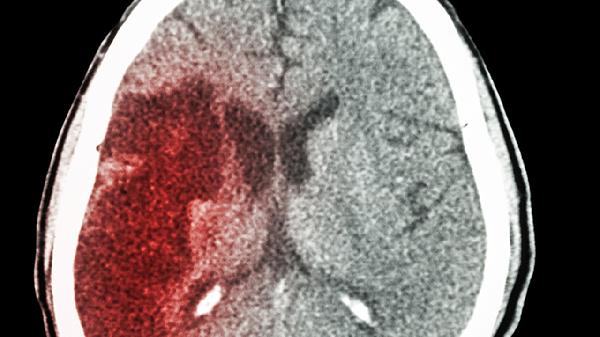

轻度脑梗患者可遵医嘱使用阿司匹林肠溶片、硫酸氢氯吡格雷片、阿托伐他汀钙片、胞磷胆碱钠片、尼莫地平片等药物。轻度脑梗可能与动脉粥样硬化、高血压等因素有关,通常表现为肢体麻木、言语不清等症状。建议及时就医,在医生指导下规范用药。